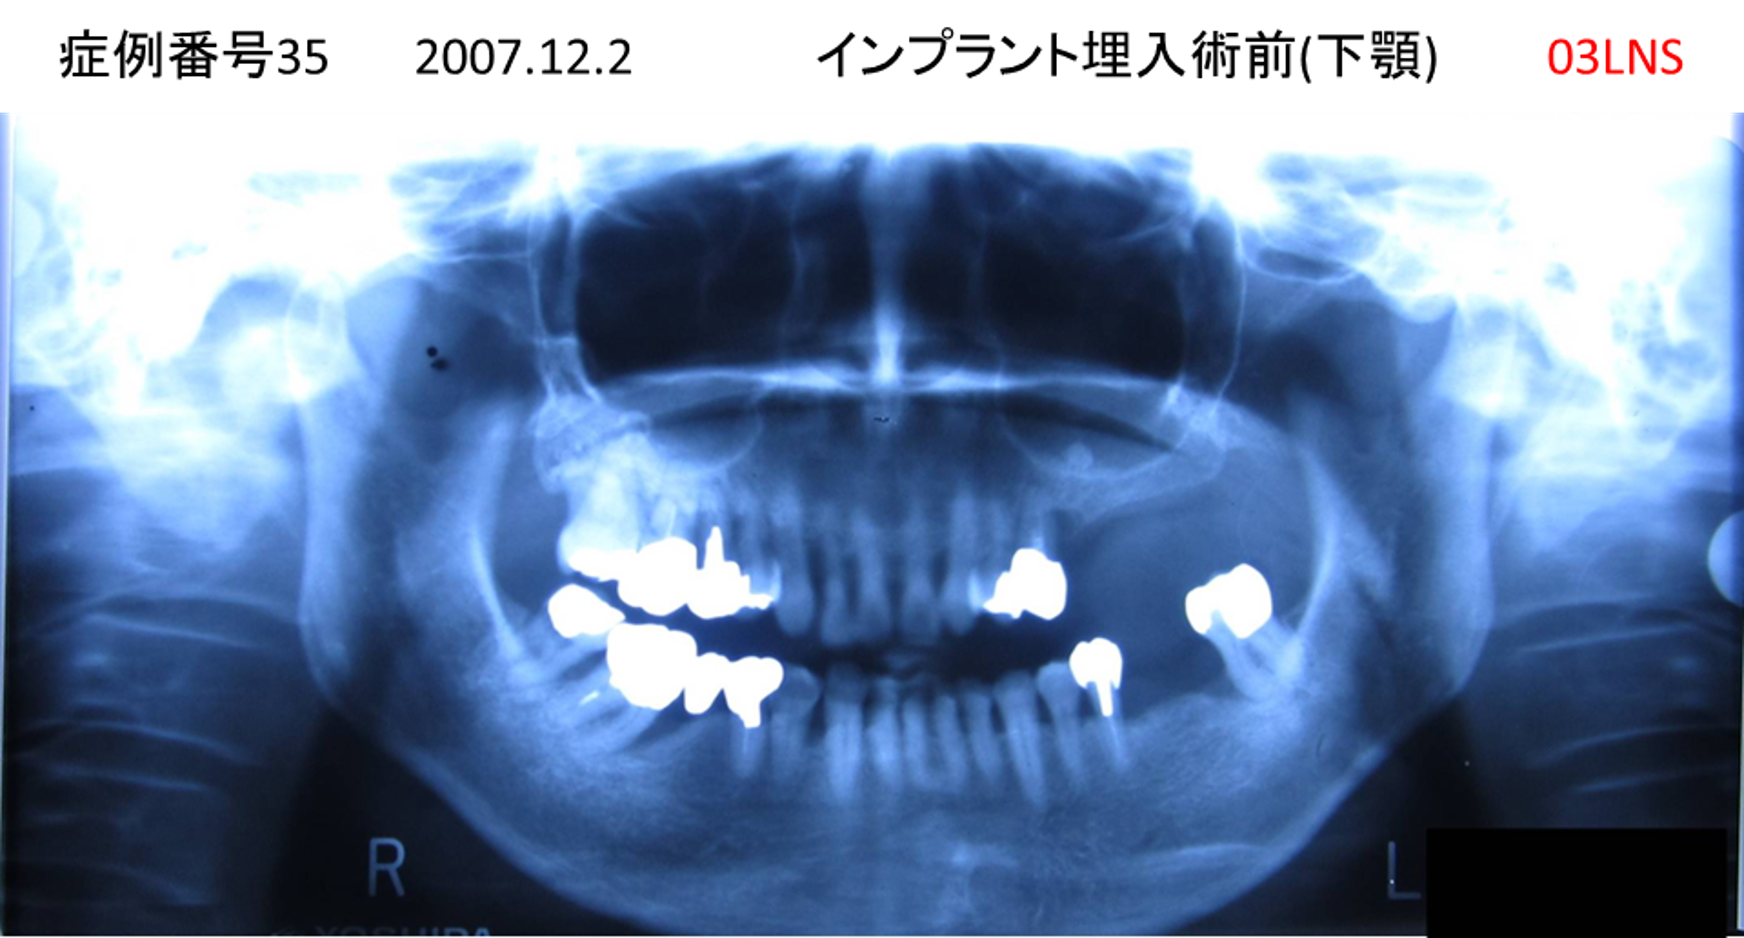

義歯が合わない、噛めない患者様のインプラント症例

| 治療名称 |

インプラントコーヌステレスコープ |

| 治療費用 |

270万円+税 |

| 治療期間 |

4か月 |

| 患者さんの症状(主訴) |

義歯が合わない、噛めない |

| 治療内容 |

インプラント、義歯作製(コーヌステレスコープ) |

| 治療結果 |

しっかり噛めるようになった。見栄えが良くなった。 |

| 治療の注意点(リスク/副作用) |

義歯が壊れた場合、インプラントが壊れた場合は再治療が必要 |